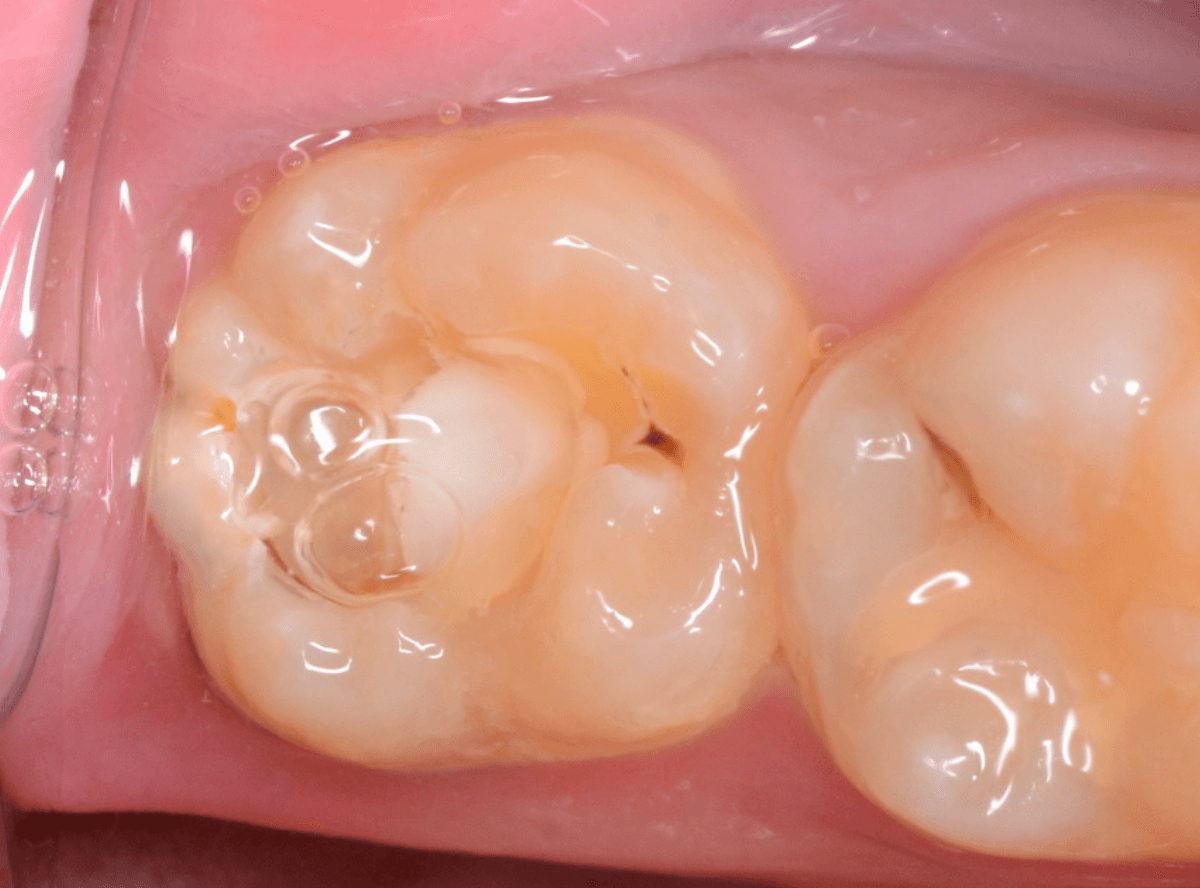

奥歯で咬んだ時に、痛みを感じるという訴えで来院された患者さんです。

パッと見は特に問題なさそうな状態ですが、大きなレジン治療がしてあり、レジンの奥もボヤっと黒っぽく見えてアヤシイ感じです。

麻酔をして、治療を開始します。

レジンを外すと、中から出血してきました。

これは、歯のスキマに歯肉が入り込んでしまったために起こってしまったものです。

おそらく、随分前から虫歯が進行していたと思われます。